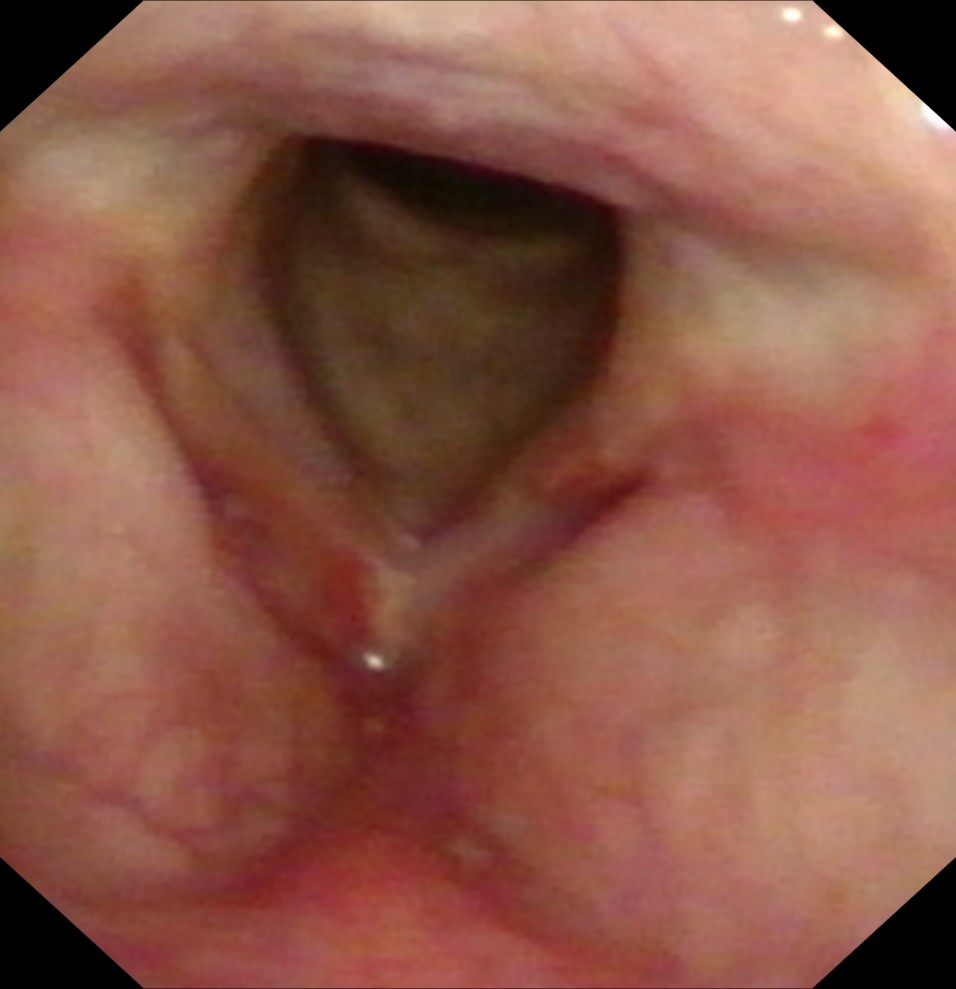

我院耳鼻喉科张建中副主任医师详细问诊后,马上予完善电子喉镜检查(如下图),根据多年的临床经验,张主任建议张大叔住院完善检查并手术治疗。

最后,完善术前检查,予安排手术治疗,术中冰冻结果提示为:左侧声带中分化鳞状细胞癌,便行“支持喉镜下左侧声带切除术”,并分别留取切缘送检,术后病理结果提示:左侧声带中分化鳞状细胞癌。